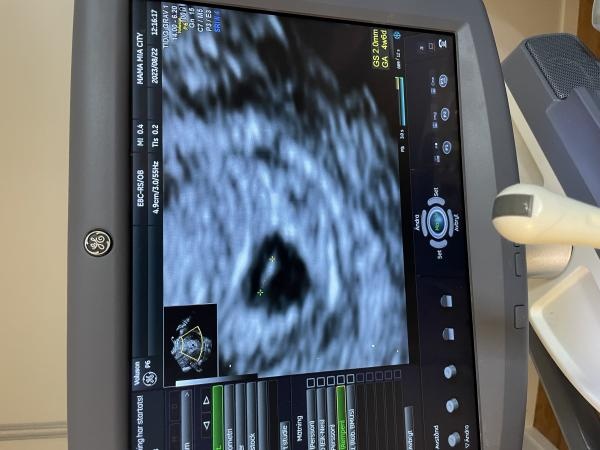

som väntat kunde man inte se något hjärta ännu men det fanns en hinnesäcken ett foster och en gulesäck iaf allt på rätt plats i livmodern. Fick en ny tid om 2 veckor för uppföljning.

upplösningne är så dålig så hon inte kunde mäta ordenligt men såhär såg det ut iaf.